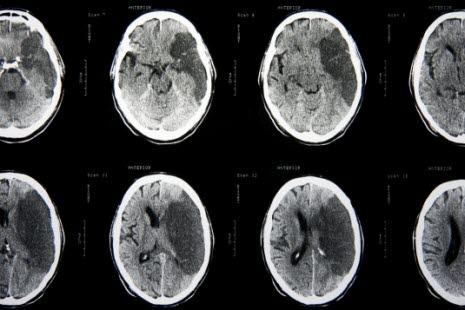

I en studie undersøkte forskerne risikofaktorer for SS ved hjelp av MR og beregnet effekten av SS på kliniske utfall hos pasienter med atrieflimmer1. Totalt ble 1200 pasienter inkludert i studien, 400 med atrieflimmer og 800 med sinusrytme. I forbindelse med rutinemessig helsesjekk av disse pasientene ble det utført MR av hjernen. Kliniske utfall hos pasientene med atrieflimmer var symptomatisk hjerneslag, demens og kognitive forstyrrelser. Observasjonstiden var 66.7 (+/- 35.9) måneder, range fra 10 til 162 måneder.

SS ble påvist hos 113 pasienter med atrieflimmer (28,3%), noe som var signifikant høyere enn 53 pasienter (6.6%) med sinusrytme (p <0.001, odds ratio [OR] 5.549). Uavhengige risikofaktorer for SS hos pasienter med atrieflimmer var alder (OR 1.049), hypertensjon (OR 2.086), dyslipidemi (OR 2.073) og klaffefeil (OR 3.157).

Insidensen av symptomatiske hjerneslag i observasjonsperioden var signifikant høyere blant pasienter med atrieflimmer og SS (5.6% vs 2.7% per år, p=0.022, hazard ratio 1.787, KI 1.089 til 2.933).